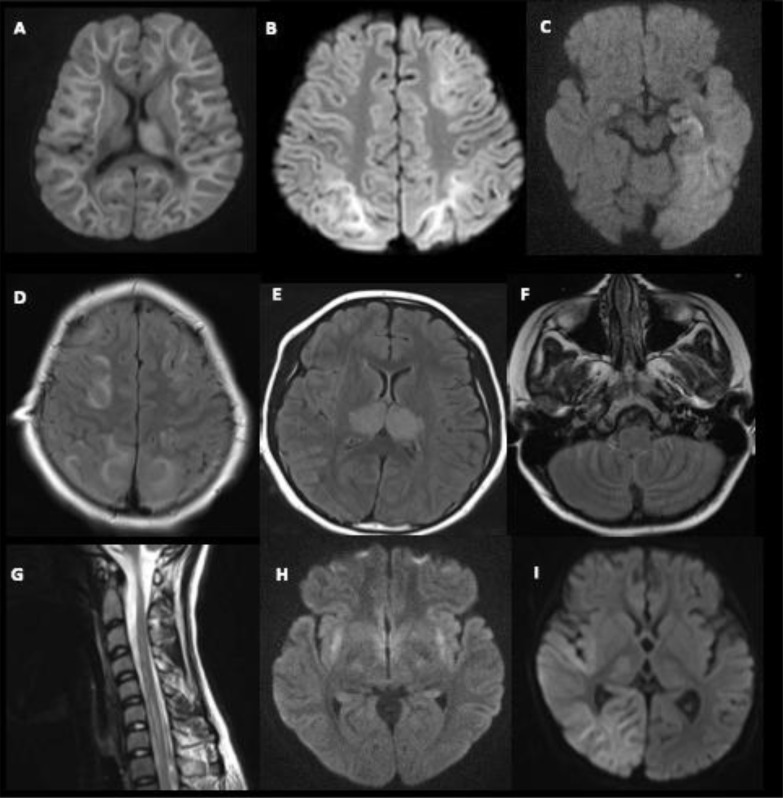

MRI brain was performed in 15 children and showed new abnormalities in eight (53%), all with IAE. The common acute MRI abnormalities were the presence of T2-FLAIR hyperintensities, diffusion restriction (each, n = 8), and gadolinium enhancement (n = 4). The spectrum of radiological features are shown in Fig. 1 A–I. Diverse clinico-radiological syndromes were diagnosed including: ANE (n = 1), acute encephalopathy with biphasic seizures (AESD) (n = 2), posterior reversible encephalopathy (PRES) (n = 1), hemiconvulsion hemiplegia syndrome (HHS) (n = 1), and cerebellitis.

Fig. 1.

Selected MRI images showing the spectrum of imaging abnormalities in Influenza-associated encephalitis/encephalopathy. A–I. A: Symmetrical diffusion restriction in the subcortical white matter and left thalamus (MRI: axial, DWI) in a 4 year old girl with acute encephalopathy with biphasic seizure disorder and late diffusion restriction (AESD) and Reye-like syndrome (Case 7). B: Symmetrical diffusion restriction posteriorly and left frontal lobe (MRI: axial, DWI) in a 2 year old girl with AESD (Case 9). C: Diffusion restriction in the left temporal lobe especially subcortical white matter (MRI: axial, DWI) in a 1.3 year old girl (Case 10). D: T2 hyperintensities in the posterior white matter (symmetrical) and patchy subcortical frontal white matter (MRI: axial T2 FLAIR) in a 7 year old boy with posterior reversible encephalopathy syndrome (Case 5). E: T2 hyperintensities in bilateral thalami which are swollen (MRI brain: axial, T2) in a 13 year old girl with acute necrotising encephalopathy. F: Prominent gadolinium enhancement of the cerebellar folia (MRI brain: axial, T1 with contrast) in a 6 year old girl (Case 6). G: Longitudinal T2 hyperintensity involving C3–7 (MRI cervical spine: sagittal, T2) in a 14 year old girl with encephalitis (Case 1). H: Diffusion restriction involving bilateral external capsule/claustrum (MRI: axial, DWI) in a 14 year old girl with encephalitis (Case 1). I: Diffusion restriction involving predominantly the right temporal lobe white matter (MRI brain: axial DWI) in a 1 year old boy with subcortical myoclonus (Case 11).